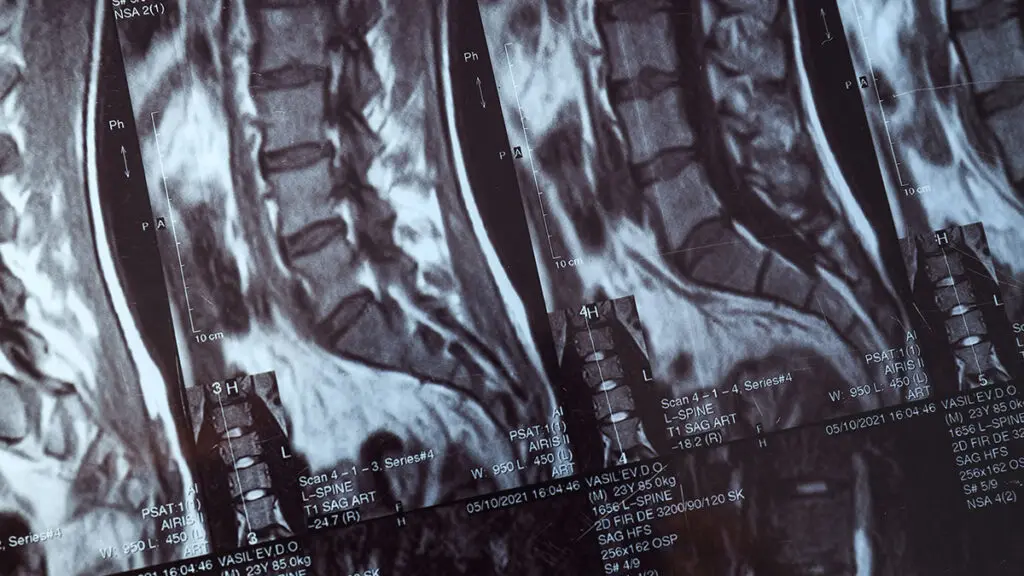

Global Spine Solutions offre a Roma approcci terapeutici avanzati e personalizzati per riabilitazione schiena, con un team multidisciplinare che integra neurochirurgia vertebrale, terapia del dolore, fisioterapia e medicina rigenerativa. Ogni percorso terapeutico viene costruito su misura sulla base della diagnosi clinica e strumentale, privilegiando le soluzioni mininvasive prima di considerare l'opzione chirurgica.

Il percorso per riabilitazione schiena disponibile presso Global Spine Solutions comprende: terapie farmacologiche mirate, infiltrazioni guidate (epidurali, periradicolari, faccette), radiofrequenza, nucleoplastica, terapie rigenerative (PRP, acido jaluronico) e programmi di fisioterapia post-procedurale. Il paziente viene seguito dall'inizio alla fine del trattamento con follow-up clinici periodici per monitorare i progressi.